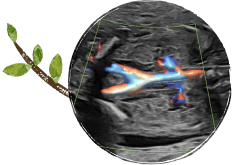

婦人科、妊婦検診、出生前検査